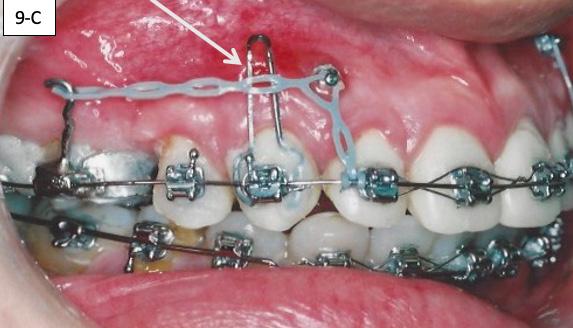

Posterior TADs were removed, when interdigitations of the maxillary cuspids and first bicuspids was achieved, we initiated the protraction of the first molars. Commercial laboratory soldered buccal power arms to the orthodontic bands on #16(3) and #26(14). These power arms allowed us to apply the force close to the center of resistance of the first molars. The TADs inserted distally to maxillary second incisors previously, served two purposes: intrusion of the anterior sextant and protraction of the maxillary first molars. The applied force was delivered with an Elastomeric chain. To prevent excoriation of the attached gingiva a .018 x .025 hand bent tissue shield was bonded to the buccal surface of #13(6) (Figure 9-A, B, C, D).

9A: Soldered power arms

FIG. 9B: Excoriation of the

FIG. oral mucosa FIG. 9C: Tissue guard, right lateral view FIG. 9D: Protraction of the first molar, left lateral view FIG. 10A: Lingual intra – Power thread, occlusal view FIG. 10B: Class II elastic, right lateral view FIG. 10C: Triangular elastic, left lateral view FIG. FIG. FIG. 12A: “W” with tail, right lateral view FIG. 12B: “W” with tail, left lateral view